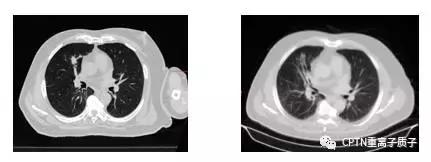

例:

早期(心脏右旁约1*2cm的肿瘤)非小细胞肺癌患者,70岁高龄,为接受过肠癌和肝转移2次手术后发生的第二个原发肿瘤。因肥胖和血氧饱和度低无法耐受肺癌手术,接受根治性质子放疗(10次),治疗过程中使用主动呼吸控制技术(ABC),保证肿瘤在治疗过程中位置稳定。放疗后半年肿瘤就几乎完全消失,CT上局部残留的阴影在PET/CT没有摄取,证实肿瘤完全消失,目前已经无瘤生存超过2年。治疗过程中和治疗结束后患者未有任何明显不良反应。